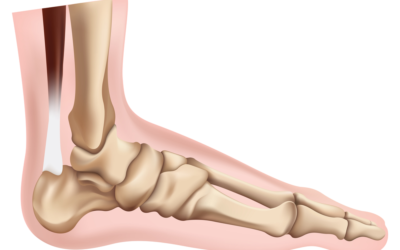

8 Things You Can Do to Help Correct Flat Feet

Flat feet are a very common foot condition, estimated to affect approximately 25% of the population in places like Victoria, BC. Also referred to as pes planus or collapsed arches, this condition causes the arches of the feet to collapse, with the sole of the foot...